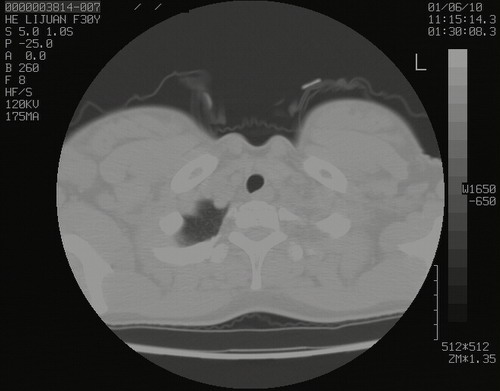

怀孕3个月时(2009-3至4月间),自述突感左侧前后胸疼痛1天,以前胸明显,随后偶感闷痛,余未见异

左肺尖脊柱旁沟肿块,境界清楚,边缘光滑,密度不均,内有多发点片状钙化,考虑良性肿瘤,骨软骨瘤或神经源性肿瘤可能,肺错构瘤不除外。

左后上纵隔见一类圆形肿块影,外侧边界清,密度不均匀,内可见点状钙化影,增强呈不均匀强化,考虑神经源性肿瘤可能。期待病理结果。